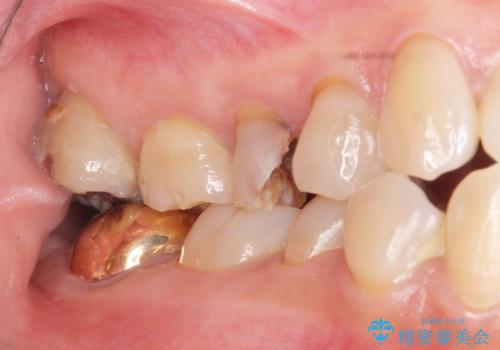

虫歯による歯の喪失 ジルコニアブリッジの製作

- 33万円(仮歯・ジルコニアクラウン×3)費用は治療当時の料金となります

ブリッジは隣の歯を削り、クラウンにしなければならないというデメリットはありますがインプラントと異なり手術をしなくてもよく、入れ歯よりも一般的にしっかりと噛むことができます。